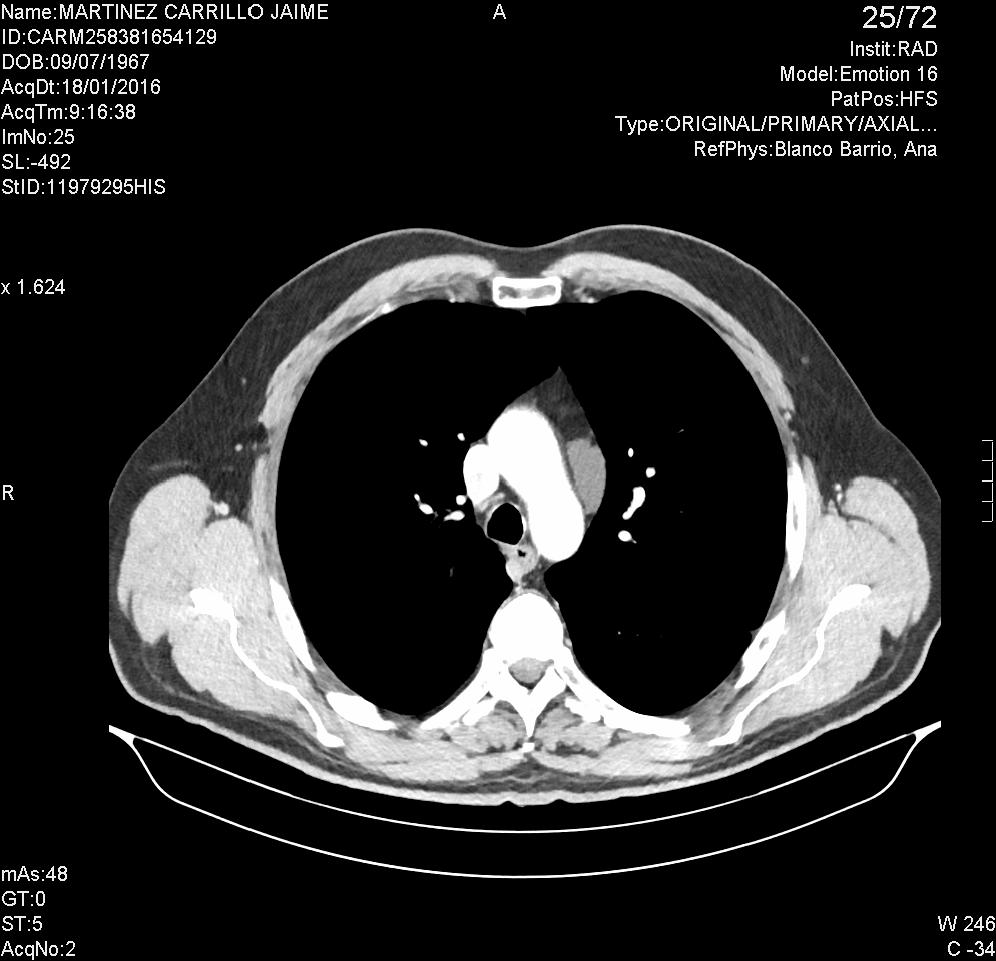

La TC es la prueba complementaria de elección para definir mejor los hallazgos obtenidos en la RX simple. La TC es una prueba de imagen que nos permite de forma rápida y precisa examinar tórax, abdomen y pelvis y que proporciona imágenes transversales en forma de secciones. Debido a la radiación que se proporciona al paciente durante la realización del TC, éste no debe realizarse de forma sistemática a menos que sea estrictamente necesario y vaya a proporcionar nuevos datos importantes que puedan modificar el curso del tratamiento.